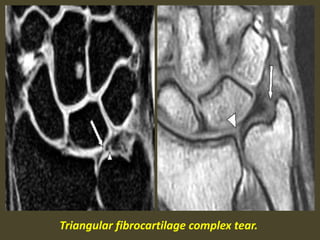

Triangular fibrocartilage complex tear.

Acute TFCC tear on FS T2-WI (A) and T1-WI (B).